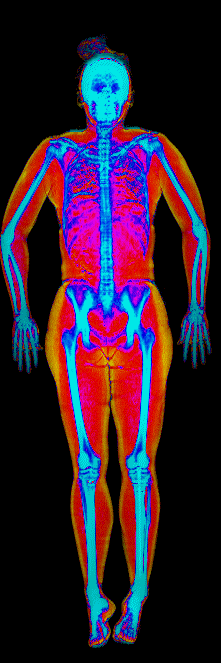

This page features real, anonymized DEXA scan images from BodyStats clients, organized by gender and body fat percentage in 5% increments. DEXA (Dual-Energy X-ray Absorptiometry) is the clinical gold standard for measuring body composition — far more accurate than scales, calipers, or visual estimates.

Each colorized scan shows the distribution of fat tissue (shown in warmer colors) and lean tissue (cooler colors) throughout the body. Compare your own DEXA scan to others in your range, or see what different body fat levels actually look like on a scan.

Female DEXA Scans by Body Fat %

15 to 20% body fat